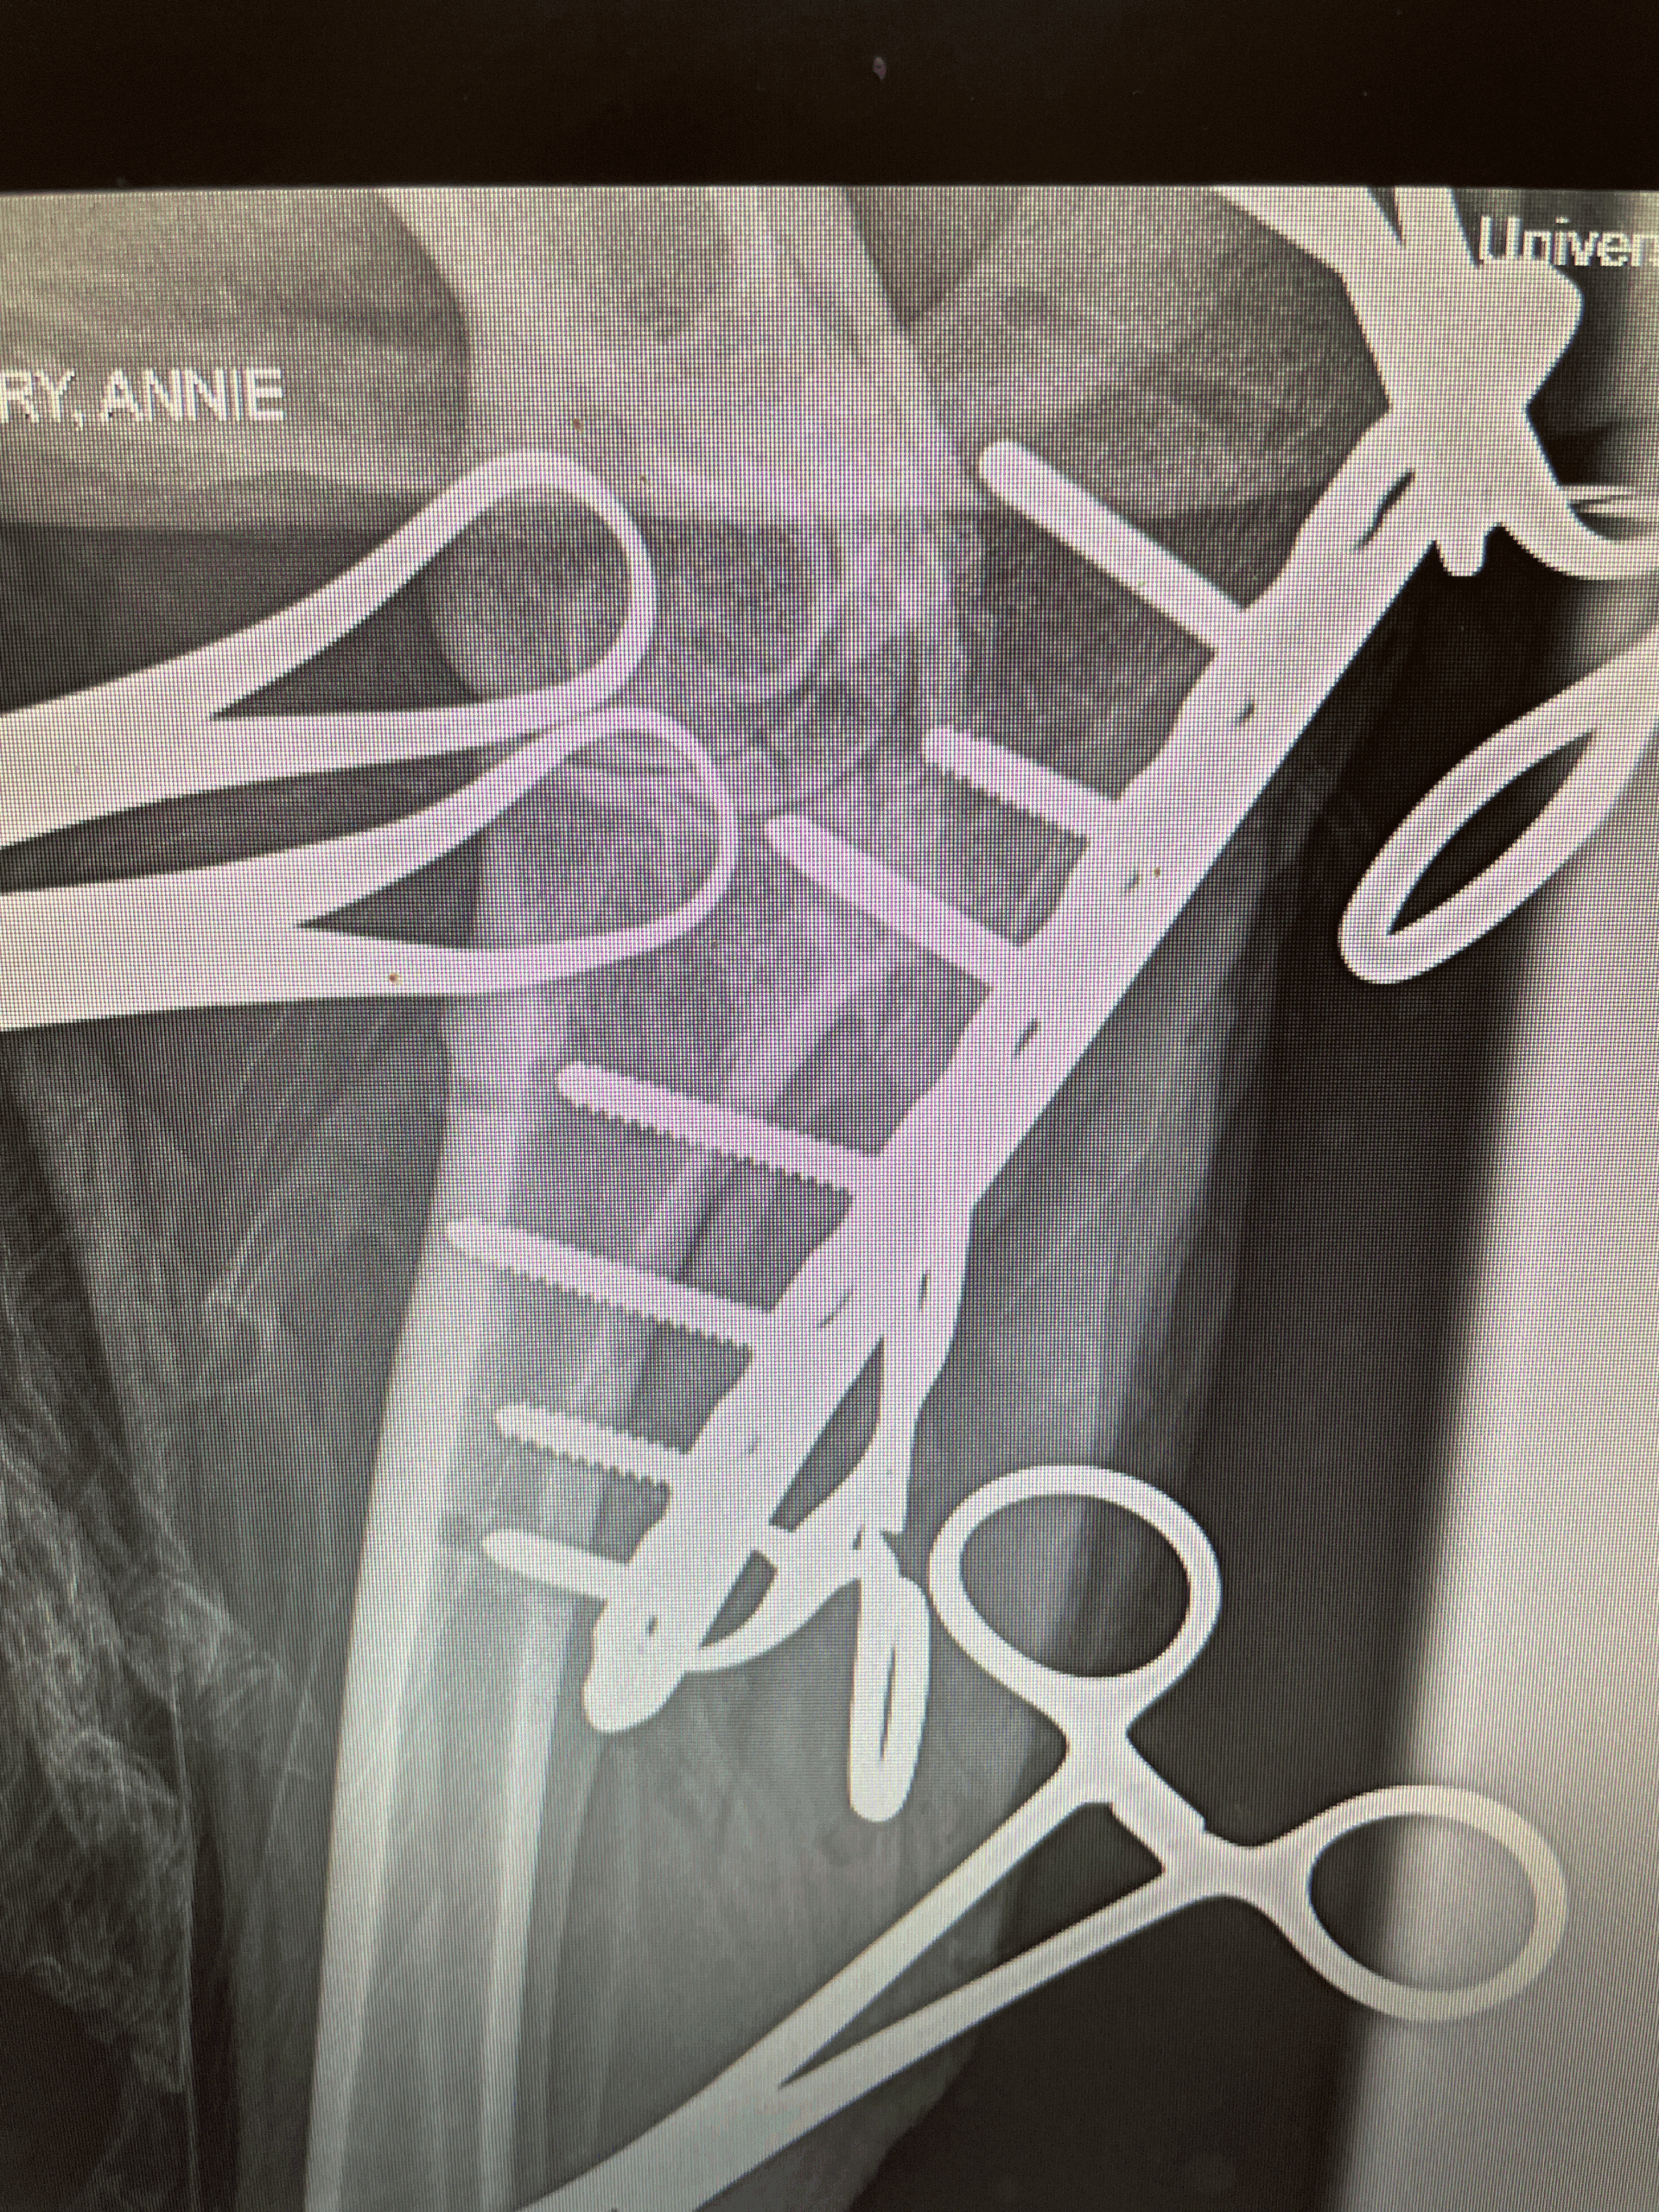

Annie

Annie post-surgery day 2

December 23, 2025

Annie Update (Post-Surgery)

December 22, 2025